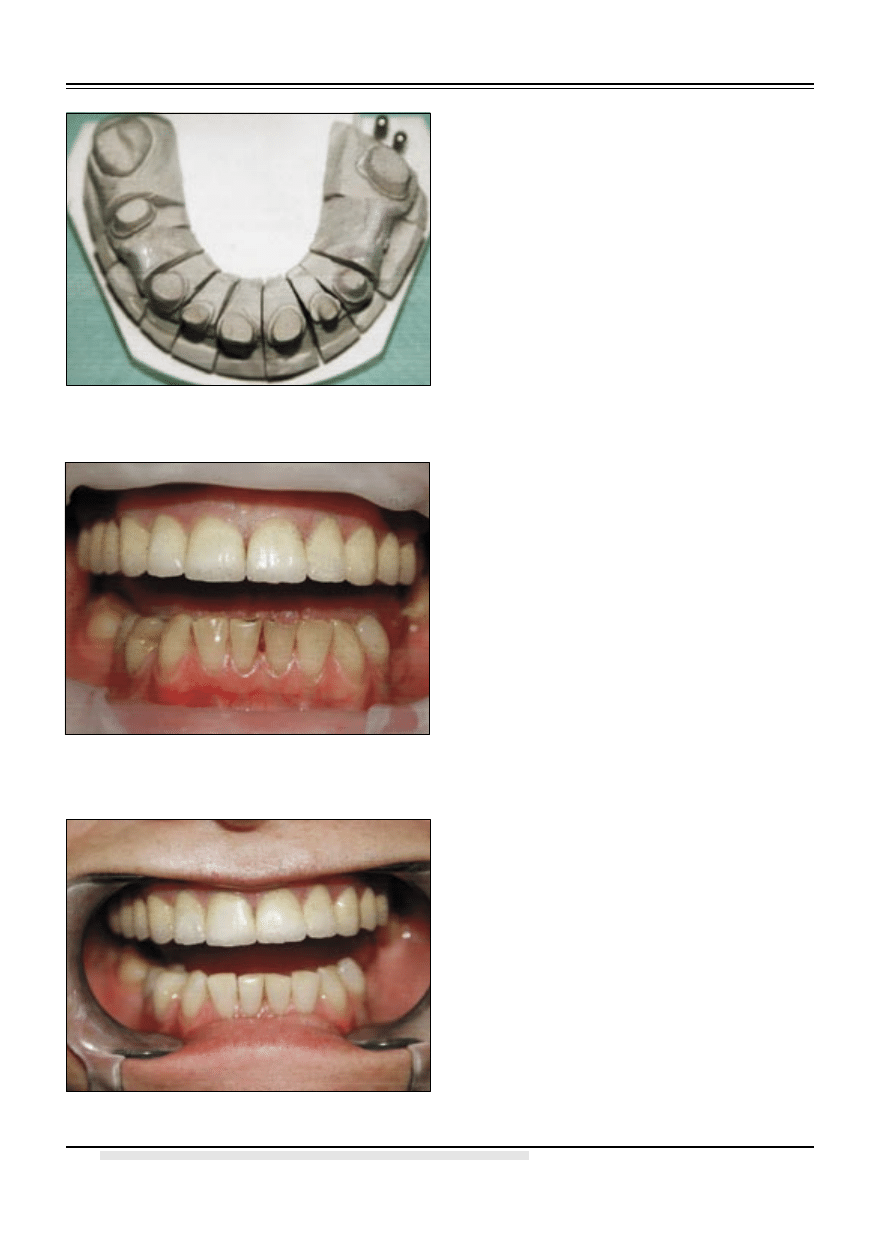

tzw. cyrkonia silikatowa (8). Gotowe uzupeł-

nienie zacementowano na cement kompomero-

wy Rely X Unicem. Następnie wybielono zęby

dolne pacjentki za pomocą szyny nakładkowej

z użyciem preparatu Opalescence 35% i 20%.

(ryc. 5 i 6) W dłuższej perspektywie zaplanowano

Ryc. 5. Stan przed wybieleniem zębów dolnych.

Ryc. 6. Efekt końcowy.